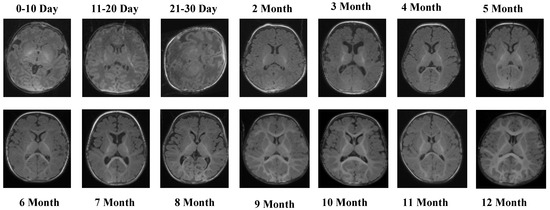

Figure 3 provides visual examples of the T2 Male sequence across all developmental groups, demonstrating the contrast-specific advantages of T2 imaging.

The T2 Male sequence included a total of 7066 images, divided into 5653 training samples and 1413 test samples. Compared with T1 data, T2-weighted images offer complementary contrast that captures different tissue characteristics, enhancing the diversity of training features. Representative MRI slices from the T2 Female sequence are shown in Figure 4.